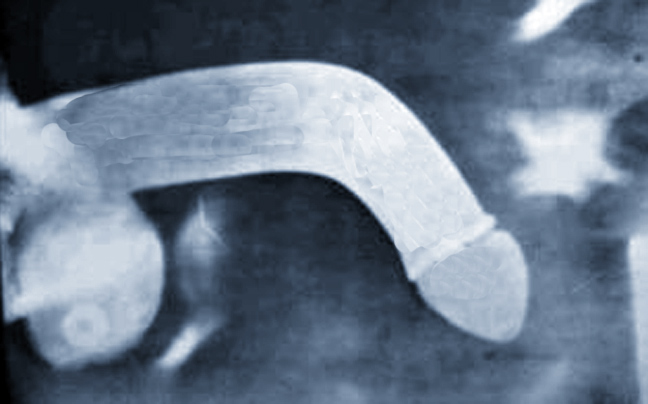

Κάταγμα στο γεννητικό του όργανο είχε υποστεί κατά τη διάρκεια σεξουαλικής επαφής ένας 52χρονος που πριν καιρό πήγε με πόνους και αιμάτωμα στο νοσοκομείο.Το πρόβλημα αντιμετωπίστηκε χειρουργικά από τους ουρολόγους και σήμερα ο 52χρονος έχει θεραπευτεί χωρίς να έχει επηρεαστεί η ποιότητα της σεξουαλικής του ζωής και χωρίς να αντιμετωπίζει πρόβλημα στην ούρηση.

Ο ασθενής στο πλαίσιο μετεγχειρητικής παρακολούθησης, ελέγχθηκε με δυναμική σηραγγογραφία μετά από τρεις και έξι μήνες με υπερηχογράφημα για την διερεύνηση ήπιας φλεβικής διαφυγής και ήπιου βαθμού στυτικής δυσλειτουργίας, η οποία μετά από ένα χρόνο αποκαταστάθηκε πλήρως.

Οι ουρολόγοι επισημαίνουν ότι σε τέτοια περιστατικά δεν συνιστάται η συντηρητική αντιμετώπιση, διότι μπορεί να υπάρχουν σοβαρές επιπλοκές. Η χειρουργική αντιμετώπιση στην συγκεκριμένη περίπτωση αποσόβησε τις σοβαρότατες επιπλοκές που θα επέφερε η συνυπάρχουσα ρήξη ουρήθρας.